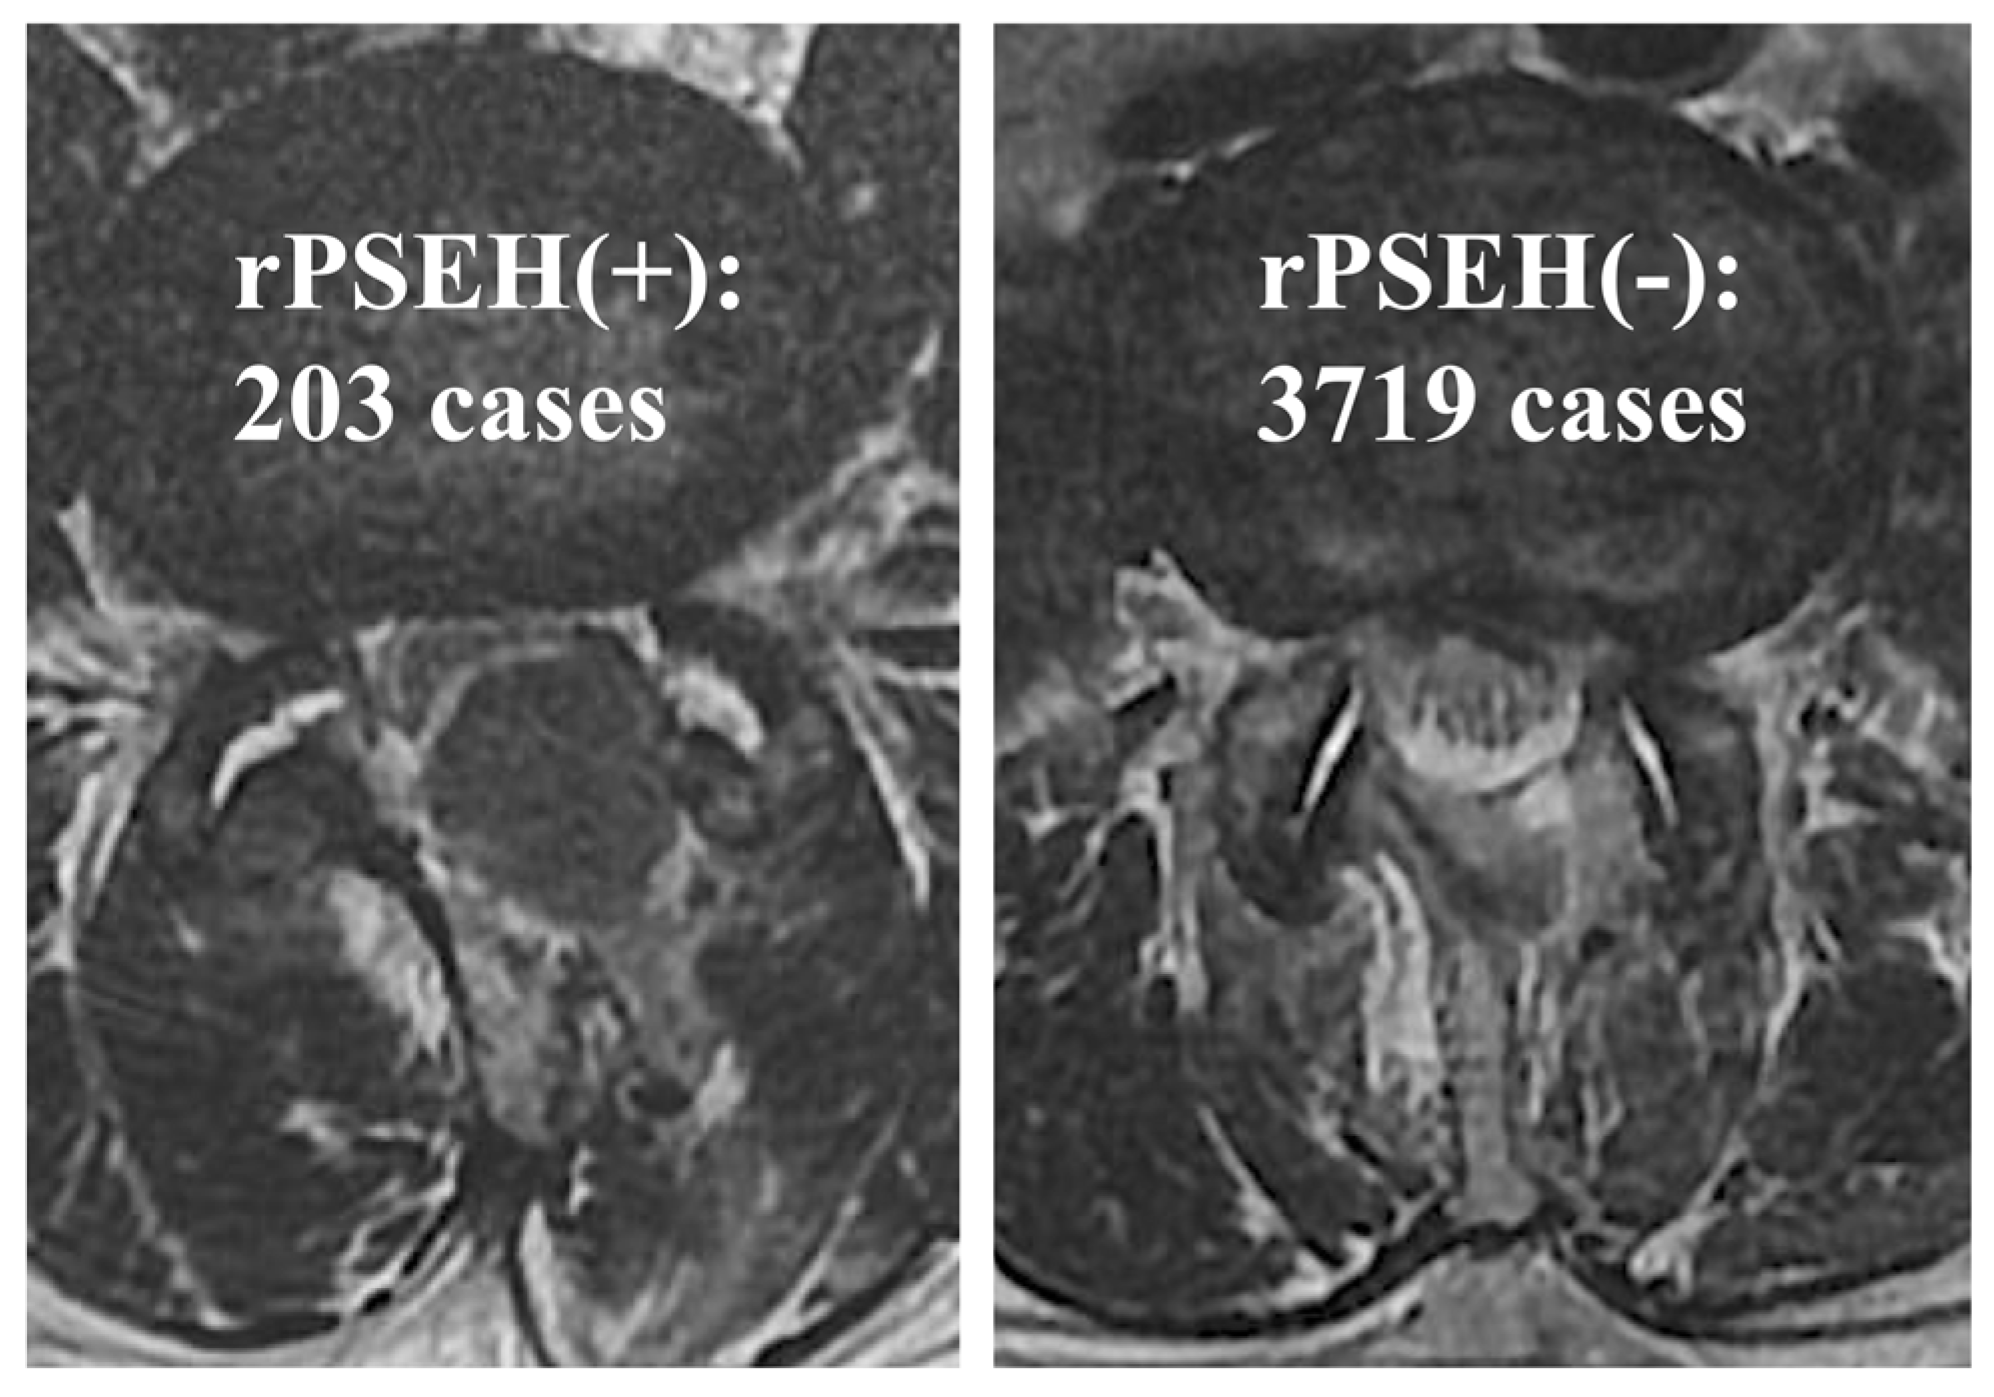

3.1. Incidence Rate of rPSEH

| rPSEH Group (n = 203) | Control Group (n = 3719) | p-Value | |||

| Accumulated surgical experiences (cases) | 1–1000 | 70 (7.0%) | 930 | 0.017 | |

| 1001–2000 | 49 (4.9%) | 951 | |||

| 2001–3000 | 48 (4.8%) | 952 | |||

| 3001–3922 | 36 (3.9%) | 886 | |||